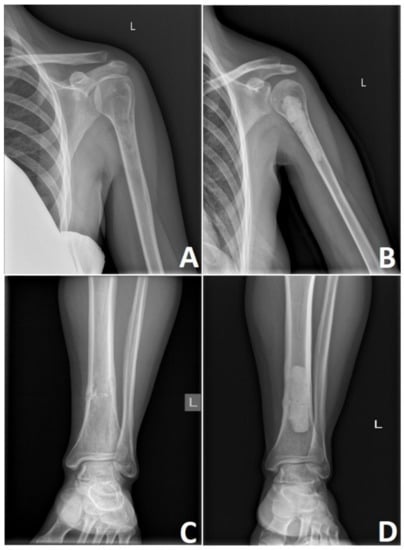

5. Surgical Treatment of Chondrosarcoma